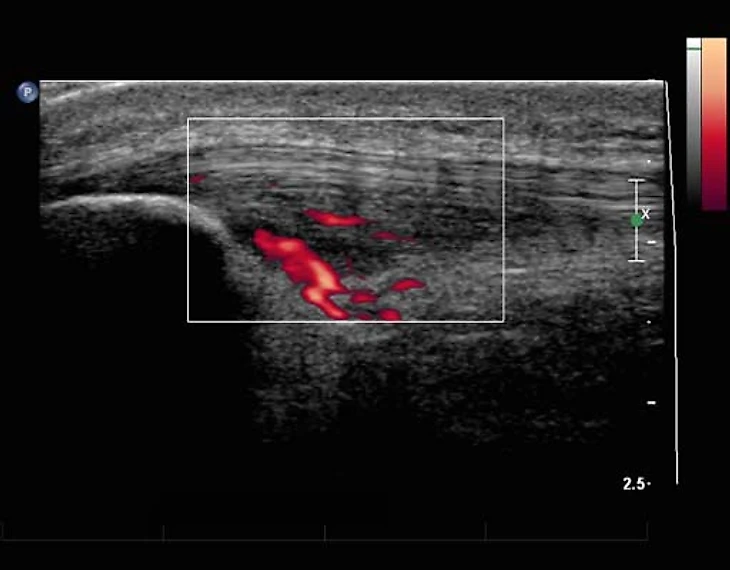

Тендинопатия — это структурные изменения в сухожилии, причем воспалительного компонента там нет, почему это так важно объясню чуть позже. Эта патология формируется постепенно, в ответ на избыточную нагрузку — любая нагрузка приводит к микротравматизации сухожилия, особенно, уровня профессиональных футболистов. Если мышца и сухожилие к такой нагрузке не готовы или получили недостаточно времени на отдых, то сухожилие не успевает восстановиться, вместо упорядоченного коллагена 1 типа появляется хаотично расположенный, гораздо менее прочный коллаген второго и третьего типа. Можно сказать, микроскопические рубцы. Прорастают новые сосуды, чтобы как-то компенсировать скорость восстановления, но вместо этого они лишь еще больше нарушают нормальную структуру сухожилия и повышают его болевую чувствительность. Так появляется характерная боль в сухожилии.

Вот, как это примерно выглядело в случае Маслова.

Как мы видим, УЗИ позволяет точнее оценить степень изменений в сухожилии, особенно это касается неоваскуляризации. Плюс, это динамический метод, то есть мы можем попросить пациента двигать ногой, сокращать мышцы бедра и оценить, как на это реагирует сухожилие. В случае МРТ мы можем оценить лишь статичную картинку. Но и у МРТ есть свои плюсы — больший объем оцениваемых тканей; позволяет оценить еще и состояние сустава, куда ультразвуковой сигнал уже не добирается. Плюс, УЗИ хороший метод только при оценке поверхностно лежащих тканей. В случае тендинопатии в других областях МРТ может оказаться точнее и более предпочтительным методом.